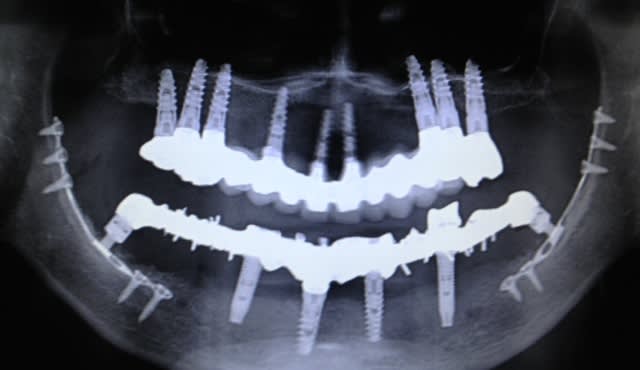

prélevements au menton et au ramus pour des greffes dans les secteurs III et IV puis pose d'implants en 34 , 36, 37 , 44 , 47 . bridge ceramo metal scellé 34 à 37 et bridge provisoire sur MUA toujours en place sur 44-47 . tout ceci a été réalisé il y a environ 2 ans .

divers problèmes sont apparus rapidement : perte de sensibilité partielle secteurIV toujours pas revenu à la normale et apparition d'un abcès au niveau de 36 il y a un an environ suivi d'un curetage au même endroit que celui pour lequel je voyais le patient en urgence .

j'ai revu le patient la semaine dernière qui voulait que je prenne la suite . j'ai fait un scan et voilà ce que çà donne .